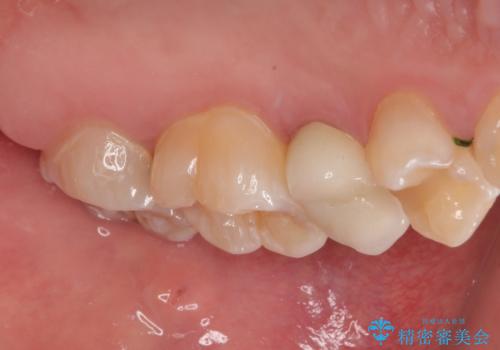

- 左上の前から5番目の金属の詰め物(メタルインレー)が取れたとのことで来院された患者様です。一時帰国中とのことで短期間での治療を希望されていました。土台はファイバーコアがしっかり入っていたため、そのまま利用することにしました。根管治療は症状もなく、レントゲン上でも病変を認めないため患者様と相談して根管治療を行わないことにしました。拡大鏡の視野下において、虫歯を除去して元々の詰め物の範囲も大きいためオールセラミッククラウンに適した形に整えました。

適合もよく、機能的に問題もなく、見た目も満足されていました。